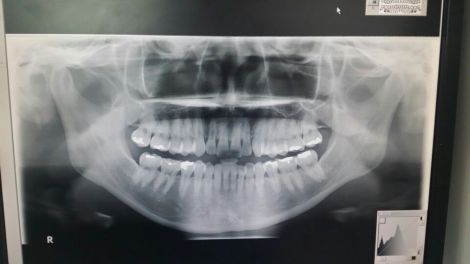

人类的牙床有个特点,牙齿咬紧后,大多是上牙包在下牙的外面,这是因为上牙弓比下牙弓大一点,都是马蹄形的。

但是,有些“地包天”的人,上牙弓偏小,磨牙长得靠里,咀嚼时离腮帮更近,比较容易咬到腮帮。

2、缺磨牙的人:腮帮子会往缺牙处长,时间久了会多出来一小点,咀嚼时容易咬到腮帮。

牙齿咬合不良是主要的原因。此外,烂牙、残冠等牙齿问题,由于边缘不整齐,甚至还很锐利,在吃饭或说话时,很容易导致腮帮被咬。